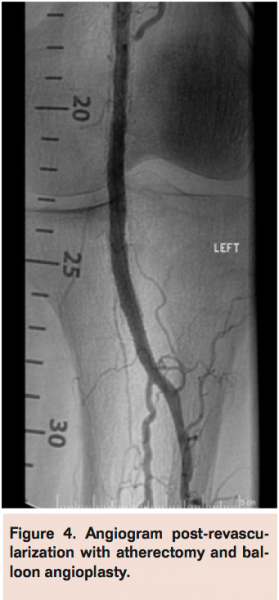

Angiogram of the left common femoral artery with runoff revealed distal left superficial femoral artery occlusion (Figure 1A) with reconstitution of the distal popliteal artery and 2-vessel runoff into the left foot via the anterior tibial and peroneal arteries (Figure 1B). Revascularization of the occlusion was performed using balloon angioplasty and stent placement (Figure 2A) with good angiographic result and runoff (Figure 2B). She had complete resolution of her claudication symptoms, but returned 1 year later with ulceration of the medial aspect of her left foot above the medial malleolus. Repeat angiogram revealed restenosis of the stent (Figure 3A) and re-occlusive disease of the distal popliteal artery stent extending into the anterior tibial artery (Figure 3B) requiring atherectomy and balloon angioplasty for successful revascularization (Figure 4). However, her ulceration progressed despite revascularization, prompting further evaluation of the etiology of her ulcer (Figure 5). A venous Doppler study of the left lower extremity revealed severe reflux of the left greater saphenous vein (Figure 6) with flow above baseline in the proximal, mid, and distal portions of up to 1.7 seconds. An incompetent perforating vein was also noted in the left calf 23 cm from the ankle and measured at 0.33 cm in diameter (Figure 7). She subsequently underwent radiofrequency ablation of the left greater saphenous vein followed by the left calf perforator with complete occlusion by ultrasound (Figure 8).